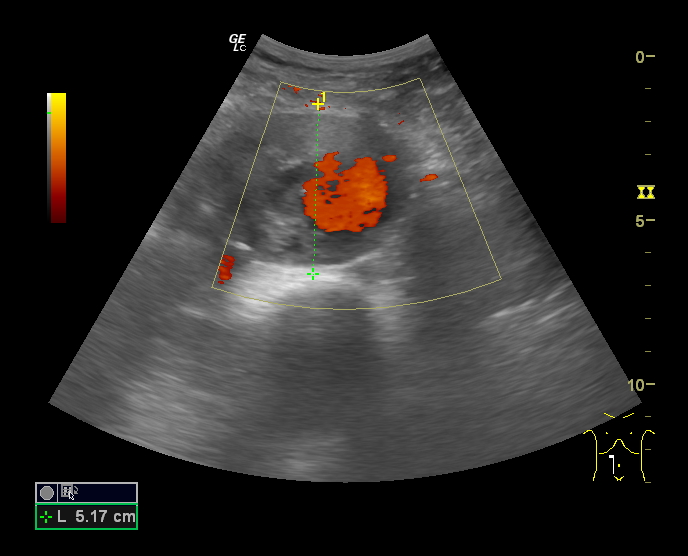

En Ecografía Clínica se aprecian, en la porción distal de la Aorta, imágenes sugestivas de aneurisma de Aorta abdominal con medidas aproximadas de 5.3 cm (anteroposterior) x 9 cm (longitudinal) con importante trombo intramural.

Diagnóstico diferencial: A la exploración física puede confundirse con otras masas abdominales como esplenomegalias o tumores. Con la eografía, la localización y captación doppler así como la pulsación característica hacen que resulte complicado confundir el diagnóstico.